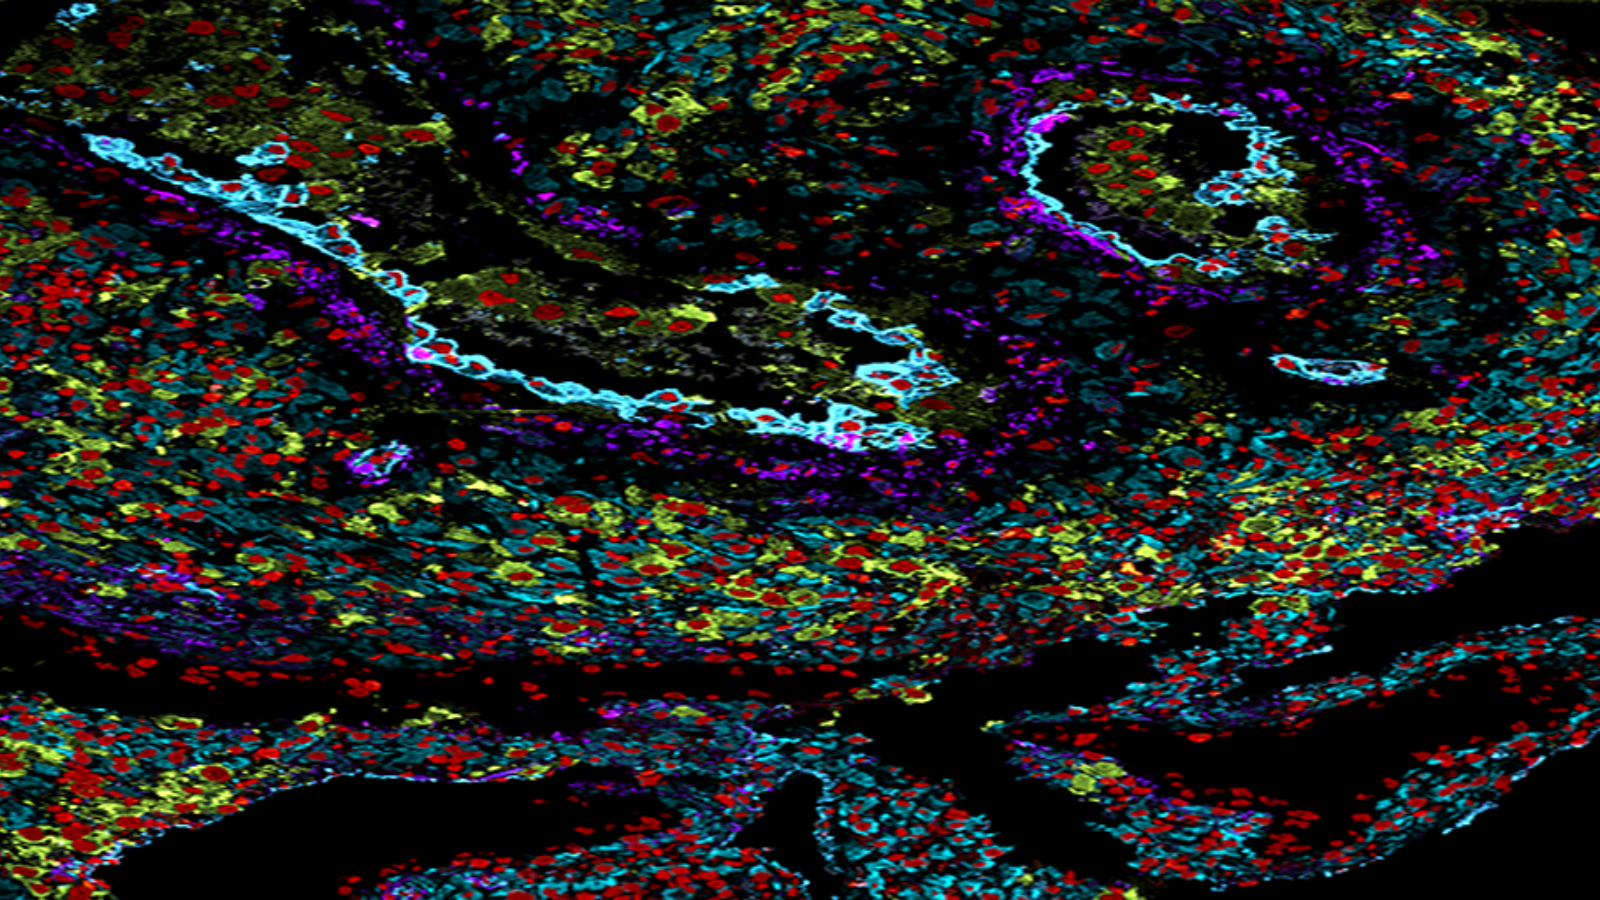

Human colon cells made by the researchers at Stanford University's Bendall lab that uses single-cell metabolic regulome profiling (scMEP).

CODEX of healthy colon, courtesy of John Hickey at Stanford

7 proteins in a section of healthy human colon tissue, courtesy of Dr. John Hickey at Stanford